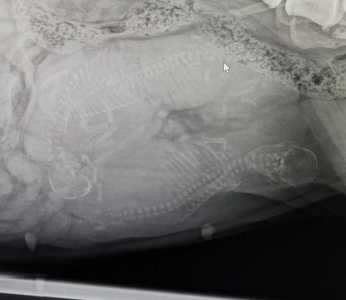

Am Dienstag, den 11.4.23 um ca. 20 Uhr wurde der H- Wurf per Kaiserschnitt zur Welt gebracht.

Wir sind dankbar für euch 3 Wunder, den es sah nicht mehr danach aus das einer Überlebt hat, aber es haben tatsächlich alle 3 Überlebt.

Wir waren gerade zur Kontrolle in der Tierklinik Wodecki, Mama und den Baby geht es gut.

Es ist ein Rüde und zwei Hündinnen.